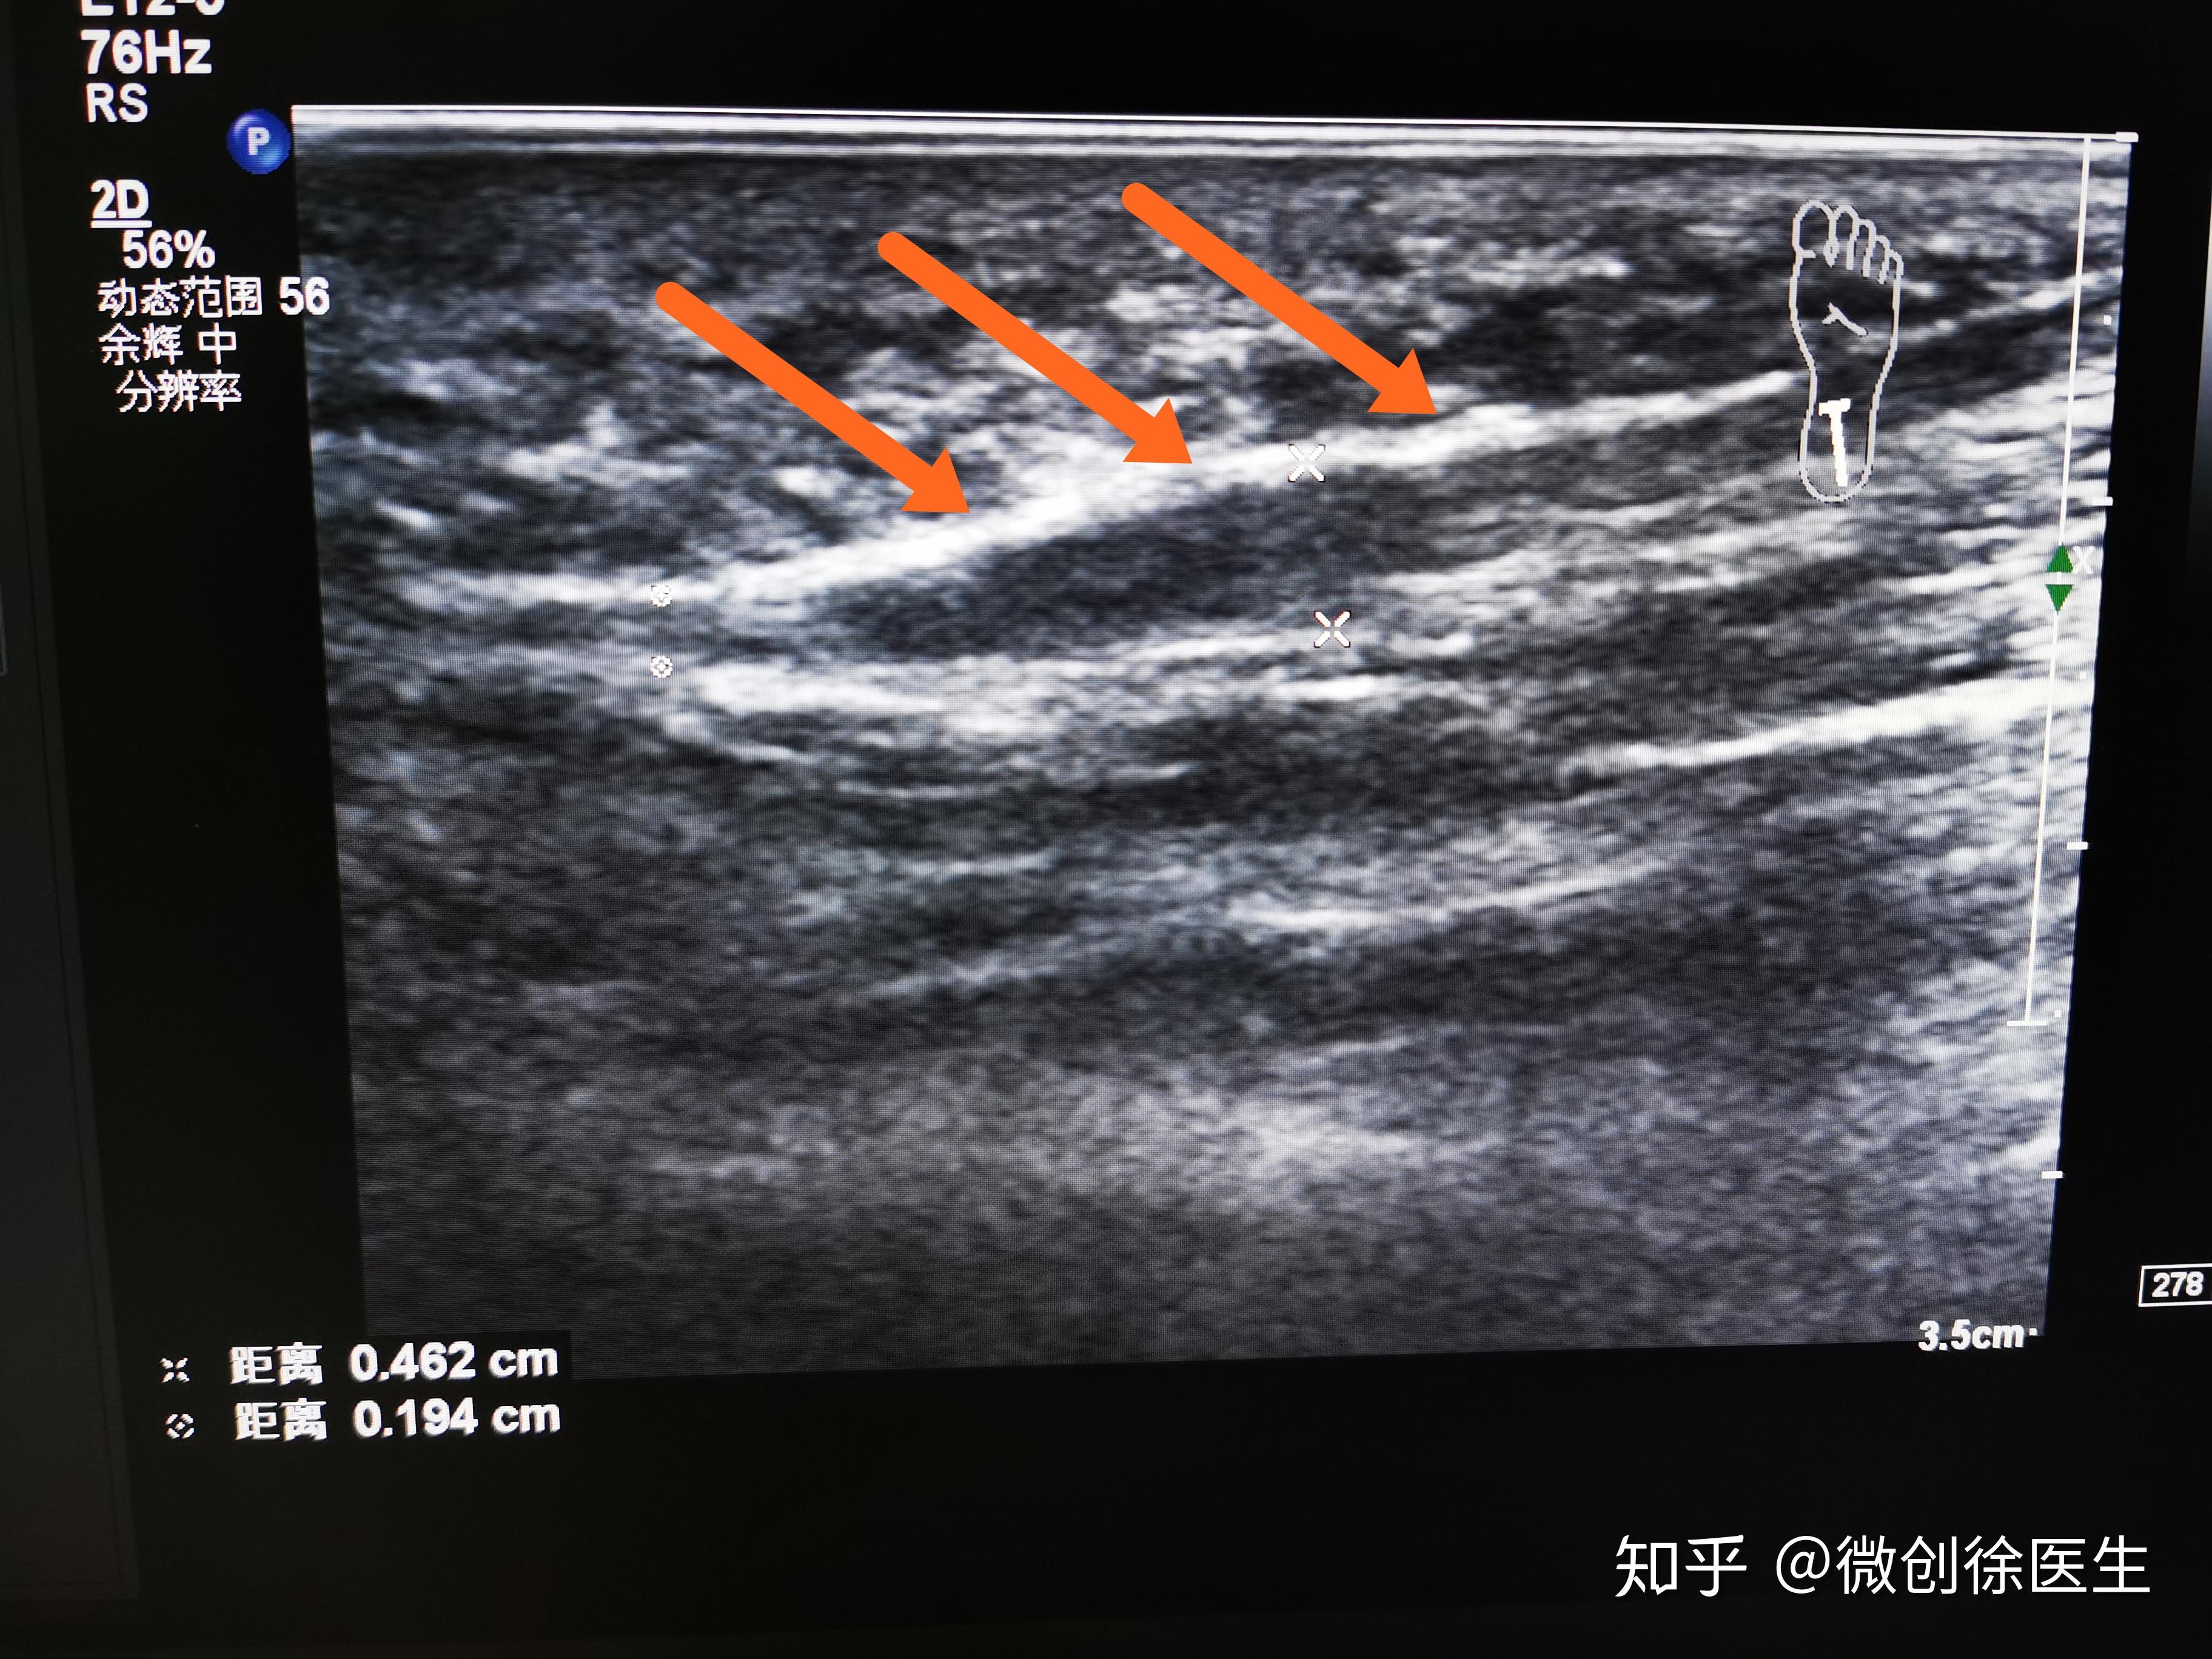

关于脚踝扭伤,你需要知道的几件事 - 知乎

图片尺寸1080x1013